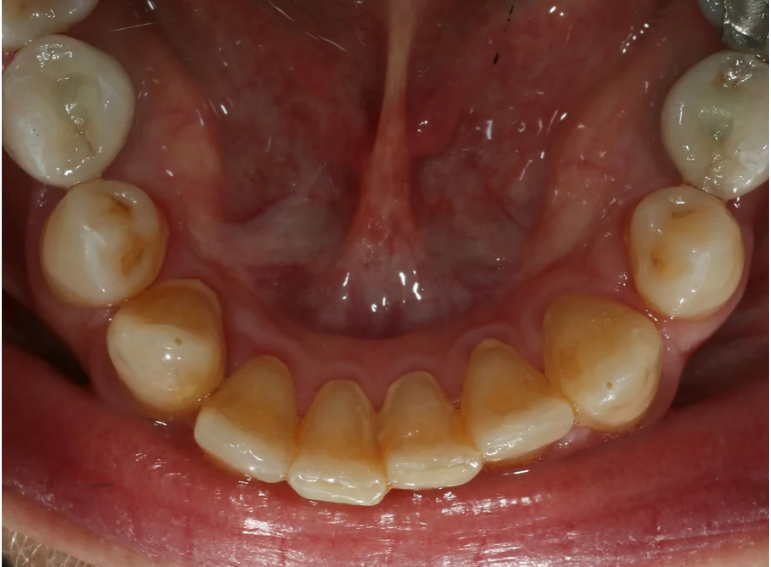

Case 9 – Implants

Placement of implants in a patient with hypodontia.